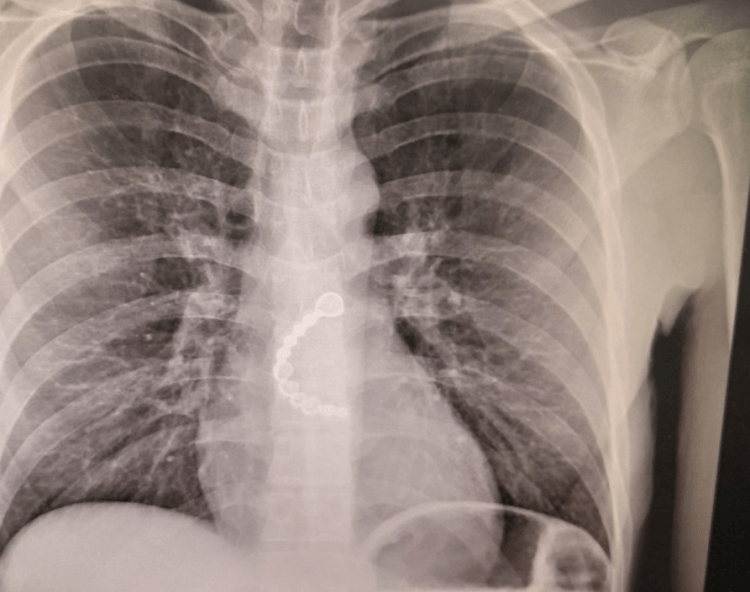

Doktori Skender Telaku ka bërë të ditur se një pacient, derisa ishte në gjumë ka gëlltitur urën metalokeramike që i kishte vënë te stomatologu.

Telaku ka bërë të ditur se ura i është larguar pa kurrfarë problemi.

“Nxjerrja e ures metalokeramike gjysmecirkulare nga perpisa (ezofagu) me endoskop. Mashkulli 35 vjec aksidentalisht, deri sa ka qene ne gjume e ka perbire uren e vene nga stomatologu disa muaj me pare. Ura u nxorr endoskopikisht pa kurfare problemi…..”, ka shkruar doktori Telaku.